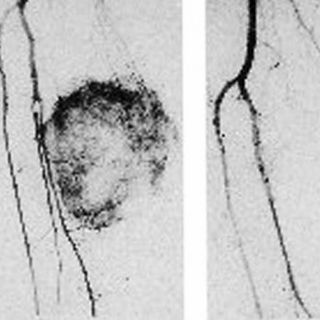

El paciente que fue tratado en el Hospital Mexico Americano es un hombre de 60 años de edad, con sarcoma en la pierna derecha en la que el procedimiento permitió hacerla independiente al resto del cuerpo. Es decir, mediante una bomba de circulación extracorpórea se aplicó un agente biotecnológico conocido como “Factor de Necrosis Tumoral”, así como una dosis de quimioterapia, lo que permitió reducir dicho tumor y facilitar la extracción.